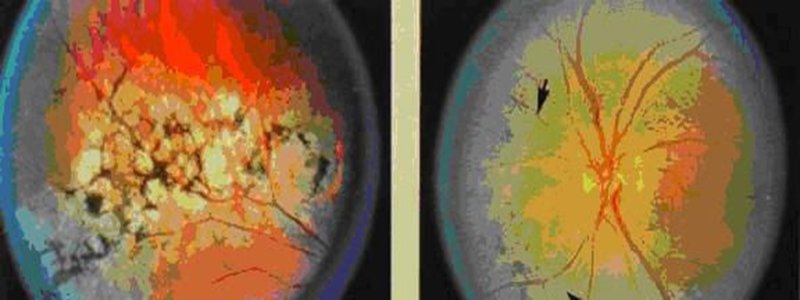

[caption id="attachment_7159" align="aligncenter" width="800"]

Viêm võng mạc sắc tố[/caption]